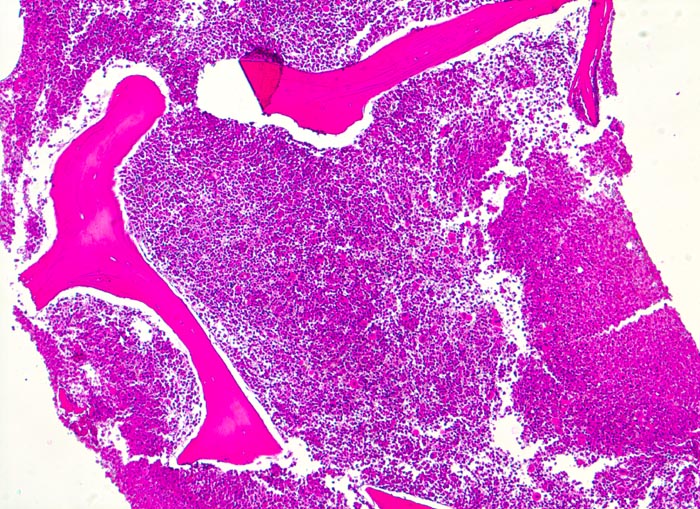

PathoPic – image database / PathoPic ID 3893 - chronische myeloische Leukämie (CML)

chronische myeloische Leukämie (CML)

Knochenmark, Beckenkamm

Massive Hyperzellularität von 100% (sogenanntes packed marrow). Vollständige Verdrängung von blutbildendem Mark und Fettmark durch Infiltration der chronisch myeloischen Leukämie (normalerweise bei 60jährigem Patienten noch ca. 40% blutbildendes Knochenmark! und 60% Fettmark)

Müdigkeit und Gewichtsverlust. Ausgeprägte Leukozytose, Basophilie und leichte Anämie. Palpable Milz.

Histologie

50

60

männlich